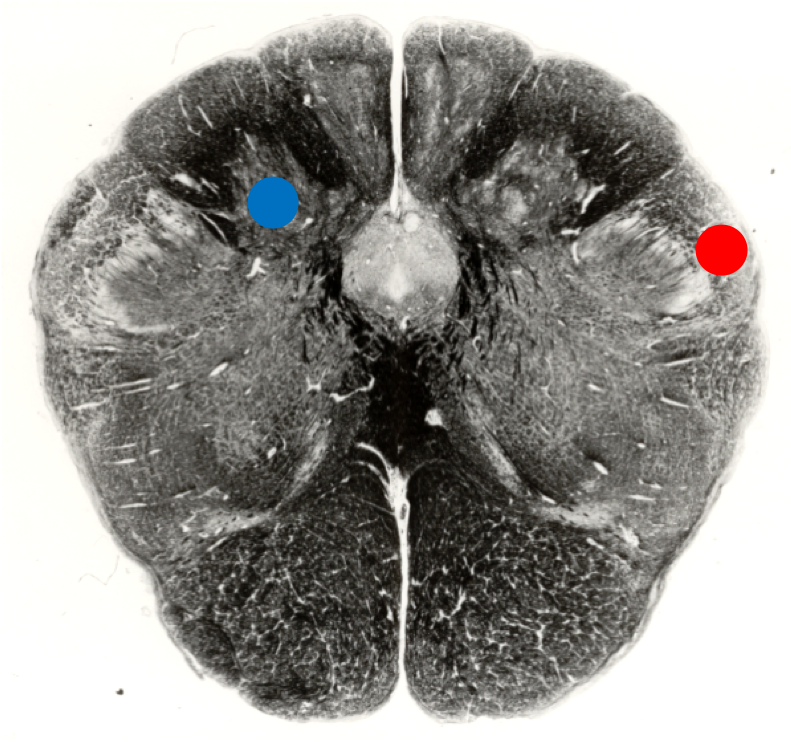

The region of the closed medulla indicted by the blue spot is the:

Cuneate nucleus

The region of the closed medulla indicted by the red spot is the:

Spinal Tract of Trigeminal